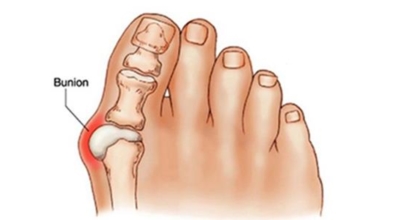

무지외반증은 엄지발가락이 두번째 발가락쪽으로 과도하게 휘고, 엄지발가락과 관절을 이루는 첫번째 중족지관절이 발 안쪽으로 치우치는 변형을 의미합니다. 관절 부위가 돌출되며 변형되기 때문에 대부분 신발을 신었을 때나 손으로 누르는 등과 같은 외부 자극이 가해질 때 통증이 발생합니다. 이번 글은 무지외반증에 관해 알려드리겠습니다.

무지외반증은 엄지발가락이 두 번째 발가락 쪽으로 심하게 휘어지며 관절이 안쪽으로 튀어나온 것을 말합니다. 무지외반증은 발가락이 단순히 휘는 정도가 아니라 튀어나와 통증을 일으키는 병입니다. 따라서 발의 볼은 넓어지며, 조금만 조이는 구두를 신어도 통증을 느끼게 됩니다. 또 엄지발가락이 두 번째 발가락을 밀어 둘째 발가락도 함께 변형되어 뒤틀어진 변형을 만들 수 있답니다.

변형이 악화되면 엄지발가락이 두 번째 발가락과 겹치거나 관절이 탈구되어 전반적으로 디디기 어려운 발이 되기도 합니다. 건강보험심사평가원의 무지외반증 환자 통계를 보면, 세대별로는 40대 이상에서 가장 많고 성별로는 무지외반증 여성 환자 비율이 남성보다 월등하게 높았다고 해요.

무지외반증의 증상은 뼈가 가장 많이 튀어나온 부분이 신발과 닿아서 통증이 있는 것이 일반적으로입니다. 돌출된 관절은 서 있거나 걸을 때 자극을 받아 빨개지고 바닥에도 굳은살이 발생되는 것과 같은 통증이 발생하게 되는데요 무지외반증은 진행형 특성을 갖고 있어 초기에는 발병 여부를 알지 못하다가 발에 변형이 시작되면 시간이 지날수록 통증이 악화돼요. 심하면 압박성 피부궤양을 동반하기도 합니다. 또 엄지발가락이 정상적인 기능을 하지 못하므로 비정상적인 보행을 하게 되고 이로 인해 발목이나 무릎, 허리 등에 스트레스를 줘 2차적인 질환을 불러올 수 있어요.